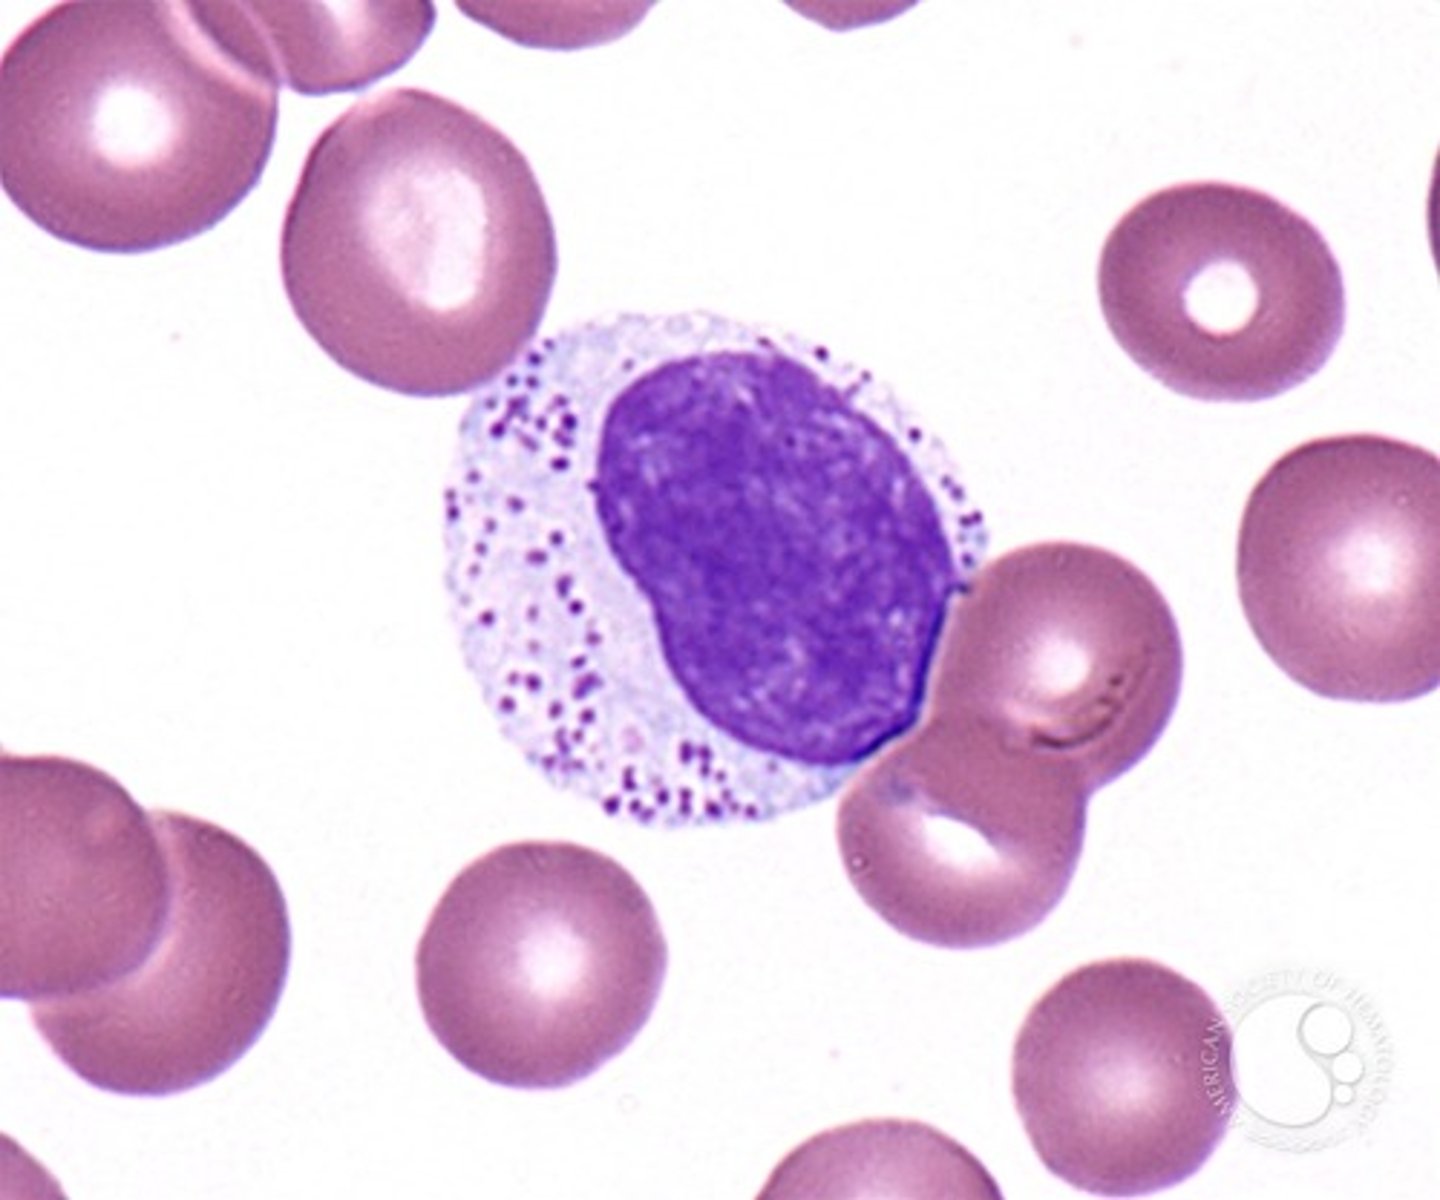

toxic neutrophils

MAMMAL

1. increase basophilia in cytoplasm

2. dohle bodies

3. vacuolated/foamy cytoplasm

4. +/- increase in cell size

dohle bodies

MAMMAL